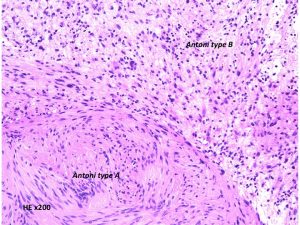

Antoni type A(密な部分)とAntoni type B(そな部分)の混在

紡錐型の核を有する腫瘍細胞で構成されます。左側の写真のように,古典的病理所見として,束状 fascicular に配列する密な組織である Antoni A Typeと網状 reticular で疎な組織である Antoni B Typeが混在するパターンを示します。神経鞘腫では多少の核の異型性がみられても悪性像とはいえません。嚢胞を形成したり,時には毛細血管拡張 simple hemangioma を思わせるような著明な血管の増生があり腫瘍内出血をきたすことがあります。